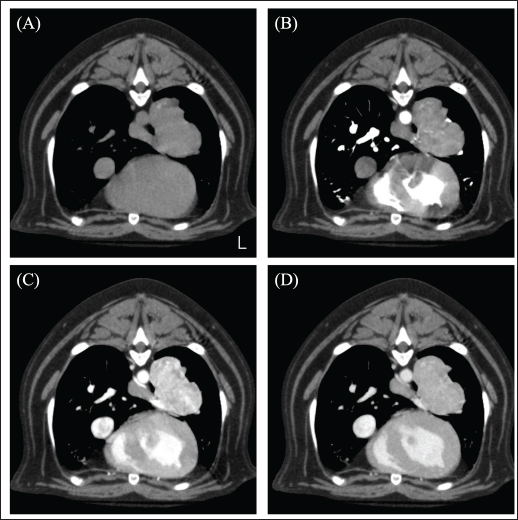

A 12-year-old spayed female French bulldog weighing 12.2 kg was visited by a veterinarian for a medical checkup. The dog had no clinical symptoms and was in good general condition; however, chest radiography revealed a mass in the left thoracic region. The dog was referred to the Okayama University of Science Veterinary Medical Teaching Hospital for close examination and treatments (day 1). The dog’s temperature was 38.3°C, heart rate was 100 beats/minute, and respiratory rate was 40 beats/minute. The non-obstructive blood pressure was as follows: systolic arterial blood pressure (SAP), 168 mmHg; mean arterial blood pressure (MAP), 124 mmHg; and diastolic arterial blood pressure (DAP), 119 mmHg. No abnormal values were observed in complete blood counts. Blood chemistry tests showed mild hypercholesterolemia (474 mg/dl), mild elevation of alkaline phosphatase (ALP; 629 U/l), and alanine aminotransferase (86 U/l) levels, and a mild decrease in blood urea nitrogen (7.5 mg/dl). The dog presented with polyurea or polydipsia. In the ACTH stimulation test, the postcortisol level was 27.8 µg/dl. Therefore, it was determined that the case presented with Cushing's syndrome as an underlying disease. Computed tomography (CT) scan (Aquilion Lightning; Canon Medical Systems Co., Otawara, Japan) performed in general anesthesia. Iopamidol (Oypalomin 300, Fuji Pharma, Japan) was used as a contrast medium [injection volume; 2.5 ml/kg (750 mgI/kg), injection time; 15 seconds]. Precontrast (before the injection of contrast medium), arterial phase (15 seconds after the start of injection), venous phase (40 seconds after the start of injection), the equilibrium phase (120 seconds after the start of injection) scans were obtained. The mass (42 × 39 × 44 mm) showed in the basilar left caudal lobe. The mass was in contact with the left cranial lobe, was strongly contrast-enhanced in the venous phase, and rapidly washed out in the equilibrium phase (Fig. 1). The right middle tracheobronchial lymph nodes were enlarged and showed a contrast-enhancement pattern similar to that of the mass in the left caudal lobe (Fig. 2). An incidentally enlarged right adrenal gland is also observed. The right adrenal gland was enlarged to 10 mm, spherical with a smooth limbus, contrast-enhanced at the limbus, peaked in the venous phase, and was attenuated in the equilibrium phase (Fig. 3). Based on the CT findings, we tentatively diagnosed the patient with a primary lung neuroendocrine tumor with lymph node metastasis. The anesthesia was stable during the CT scan, and no significant blood pressure fluctuations were observed.

Fig. 1. CT image of the chest. (A) Plain, (B) arterial phase, (C) venous phase, and (D) equilibrium phase. The mass was in contact with the left cranial lobe, was strongly contrast-enhanced in the venous phase, and rapidly washed out in the equilibrium phase.